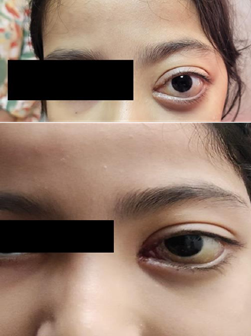

At the end of this first course, there was spectacular regression of the tumor, with marked reduction of dystopia and proptosis (Figure 3).

Figure 3: After six months of therapy using sirolimus, we note a good outcome with regression of the haemorrhagic protrusion.